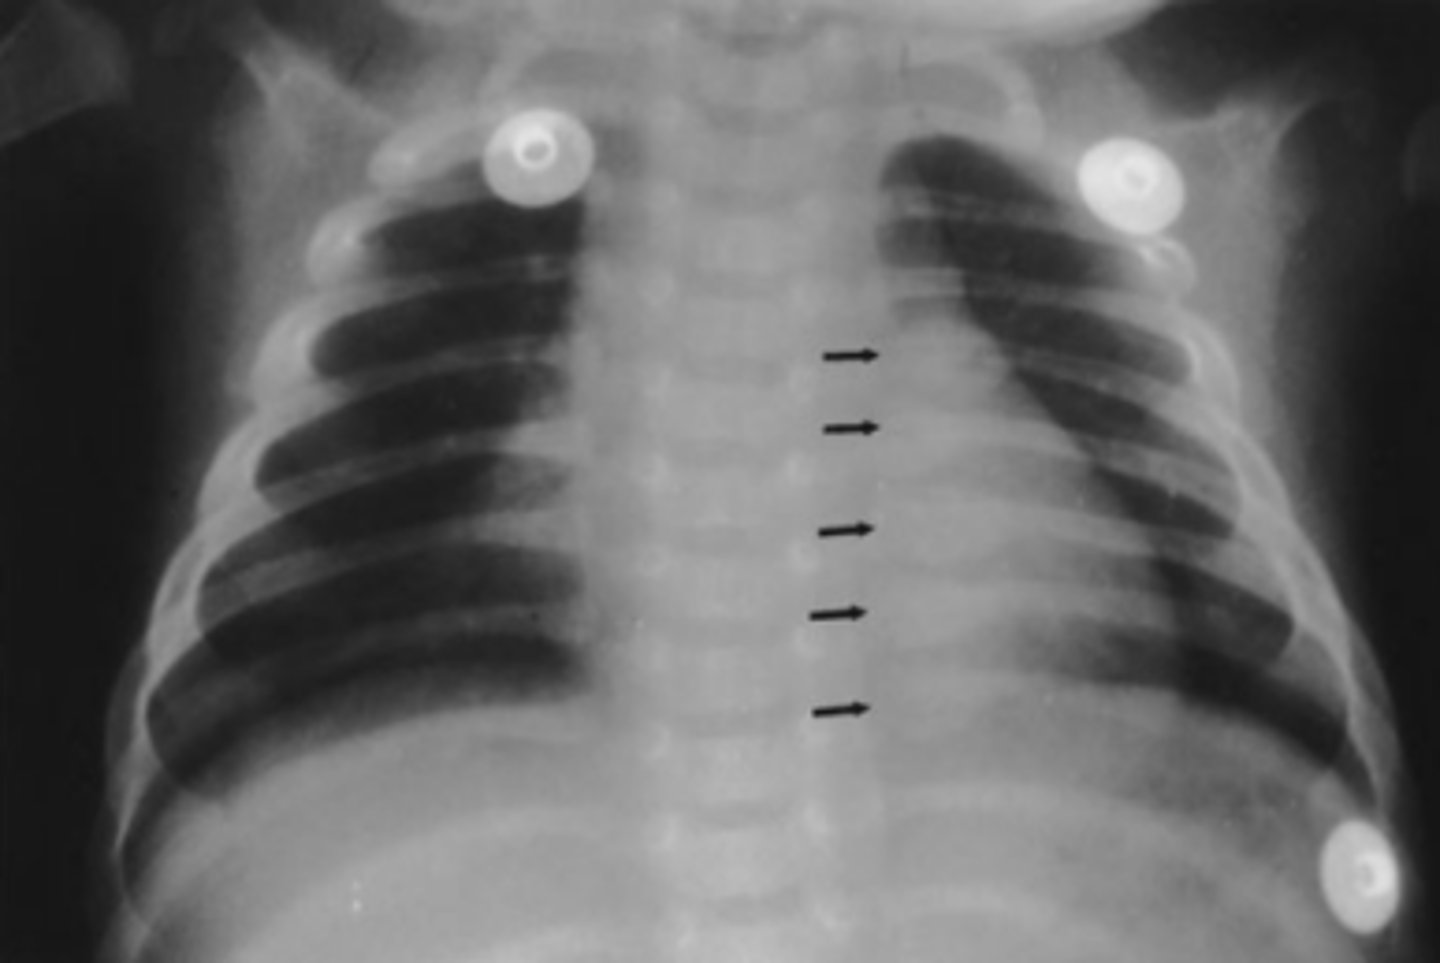

Infant with low-grade fever. You obtain a chest radiograph to evaluate for pneumonia (frontal view of the chest).

You interpret the chest radiograph for Case 6-2

(Figure 6-9) and render the following opinion:

A. Normal chest radiograph

B. Round pneumonia

C. Healing rib fractures

D. Pneumothorax

answer

C.

Unfortunately these are healing rib fractures in an infant (note the calluses). Suspected child abuse and an immediate CPS call.